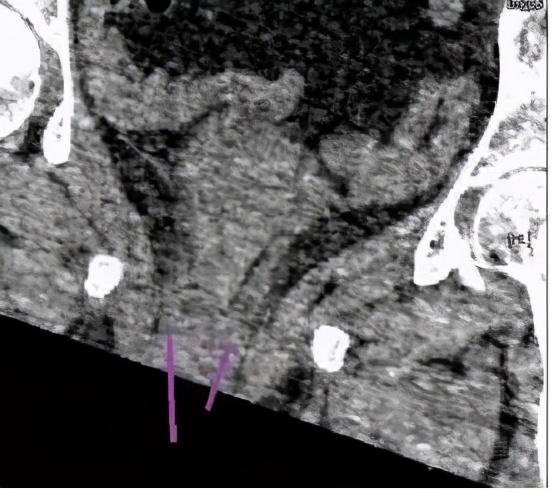

在增强CT检查的时候,得到了如下检查图像

检查图像显示,该病人的双侧输尿管于膀胱开口处过低,还伴有左侧部分双肾盂、输尿管畸形,这些图像给我们的印象是:是不是存在异位开口的可能?

输尿管异位开口是指输尿管开口不在膀胱三角区两侧的先天性畸形。

双肾双输尿管并输尿管口异位80%以上见于女性,多伴有重复肾输尿管畸形。

针对该病人,虽然病人不存在尿*禁失**的症状,但是依据影像学表现,诊断输尿管异位开口还是可以的。